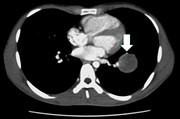

Video-assisted thoracoscopic enucleation after congenital cardiac surgery

Hideyuki Maeda and others

Journal of Surgical Case Reports, Volume 2015, Issue 9, September 2015, rjv123, https://doi.org/10.1093/jscr/rjv123